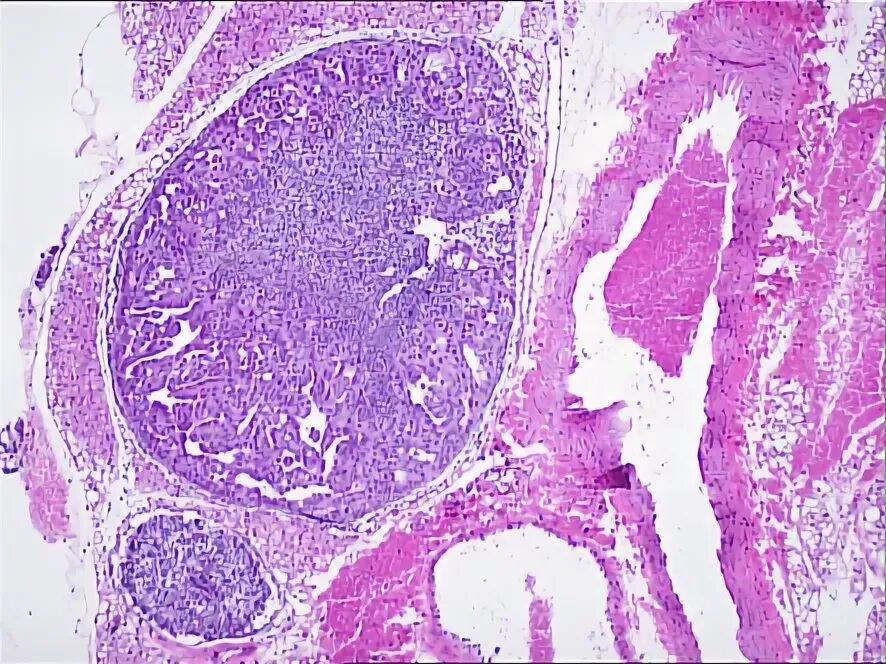

Метастазы в лимфоузлах легких